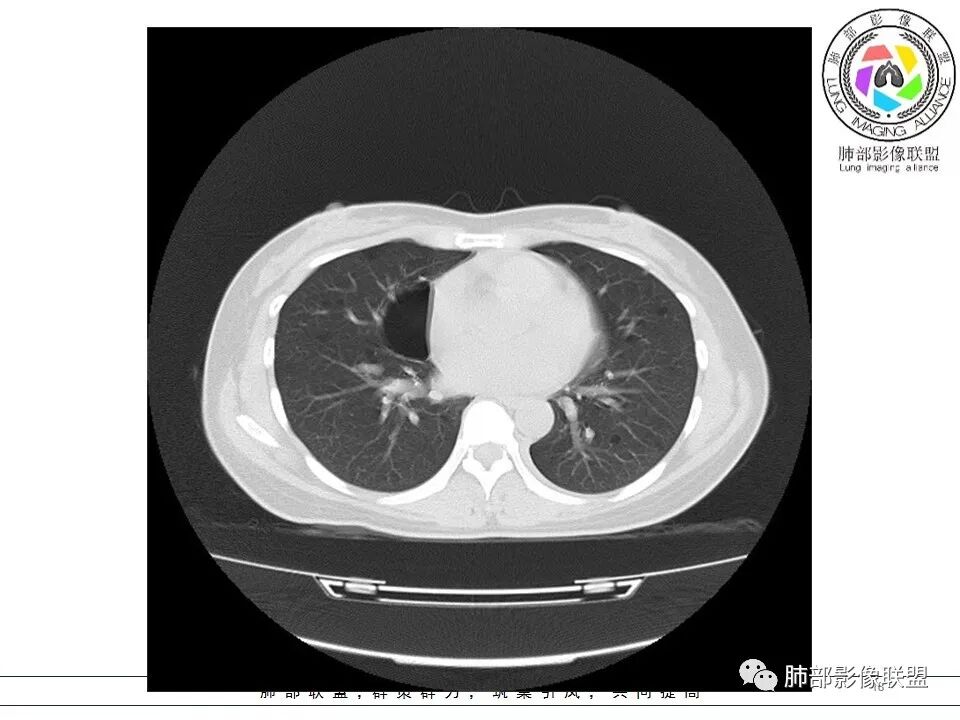

女,38岁,无症状,胸片体检发现两肺可疑病灶。

?其母亲有肺大泡,2017年手术。影像学特点:两肺胸膜下多发的大小不等囊状气腔,壁很薄或无可见的囊壁,小囊的边界比较清楚,大囊的形态比较怪异,以两下肺为著。考虑肺组织细胞增生症,鉴别肺淋巴管肌瘤病。

其母亲有肺大泡,2017年手术。

小叶中心,胸膜下囊,比较大,规则:

无其他伴随征象

常规:1、LAM 2、bhd

LAM?年龄、性别符合,囊形态符合,但是这么大囊的好像不多见,而且分布区域下肺为主的不多,没有结节,不是首选,但是不能排除

Birt-Hogg-Dubé综合征:影像符合,家族史符合